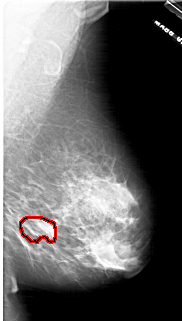

A_1771_1.LEFT_MLO

LEFT_MLO LINES 6751 PIXELS_PER_LINE 3556 BITS_PER_PIXEL 12 RESOLUTION 43.5 NON_OVERLAY

FILE: A_1771_1.RIGHT_MLO.OVERLAY

TOTAL_ABNORMALITIES 1

ABNORMALITY 1

LESION_TYPE MASS SHAPE LOBULATED MARGINS ILL_DEFINED

ASSESSMENT 4

SUBTLETY 3

PATHOLOGY BENIGN

TOTAL_OUTLINES 1

BOUNDARY